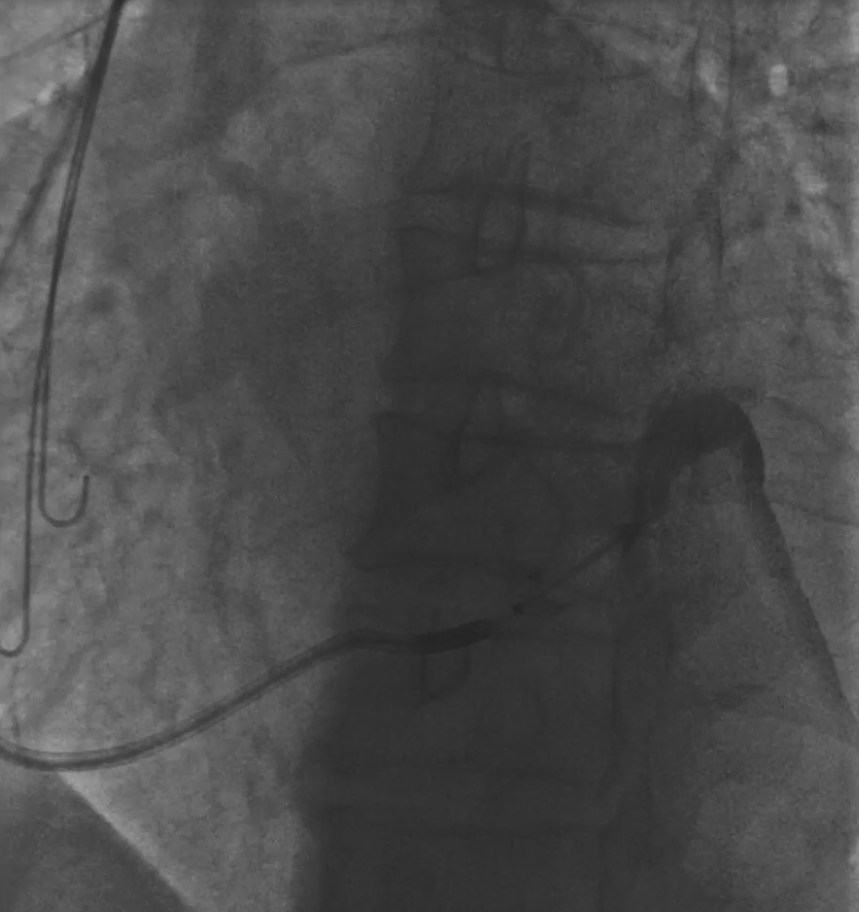

患者冠状窦开口异常,常规利用电生理十极寻找,无法进入cs,可以利用冒烟的方式确认开口位置,也可以利用患者之前的冠脉造影像来大概确认cs开口位置。

图三 冒烟寻找确认CS开口